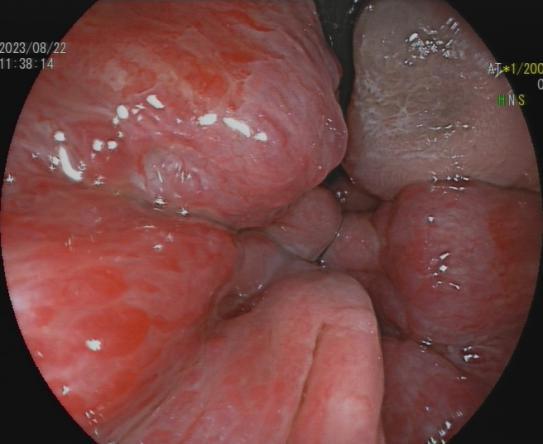

3.早期消化道肿瘤ESD技术

内镜下粘膜剥离术(ESD),具有超级微创、安全性高、住院时间短及费用低等优势,治疗早期胃癌、食管癌、大肠癌等病变,5年生存率超90%。

直肠巨大绒毛状腺瘤 内镜下粘膜剥离过程

粘膜剥离术后创面 剥离的巨大腺瘤